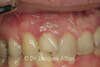

Etat initial : L’incisive latérale droite est à extraire

Extraction et pose de l’implant dans la même séance

Réalisation d’une infrastructure et d’une prothèse

provisoire en céramique réalisée par CFAO au cabinet

dans la même séance que les extractions